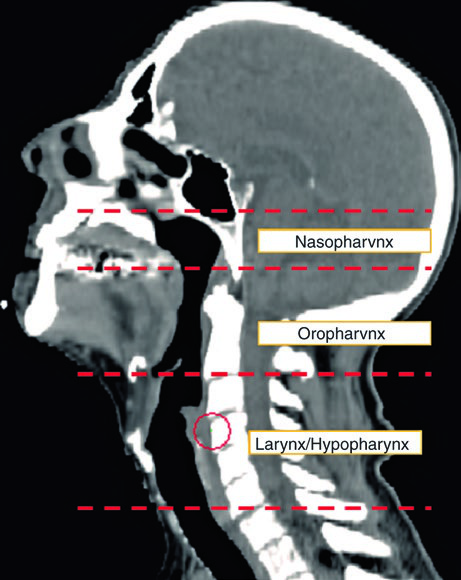

O mínimo aceitável inclui: exame físico detalhado com teste de nervos cranianos, nasofaringolaringoscopia flexível visualizando nasofaringe, orofaringe, laringe e hipofaringe, além de TC de alta resolução com contraste. Um exame cuidadoso da pele e do couro cabeludo também é essencial — melanoma e outros primários cutâneos são diagnósticos diferenciais reais.

A visualização em cortes sagitais (Fig. 10.2) é particularmente útil para confirmar a extensão craniocaudal correta dos volumes de mucosa — nasofaringe, orofaringe e laringe/hipofaringe — e assegurar que não haja lacunas entre os CTVs adjacentes. O isocentro radiográfico serve como referência geométrica para o planejamento.